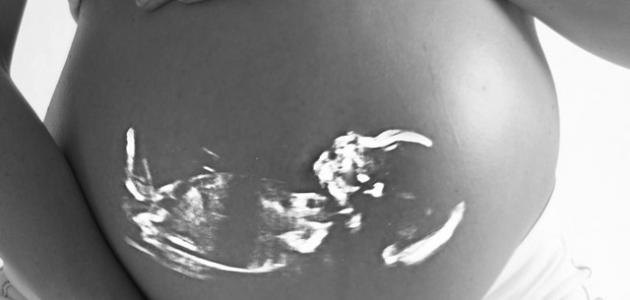

علامات توقف نبض الجنين في الشهر الثاني

لا شكّ أنّ الحمل يعتبر من أكثر الأمور التي تشعر العائلة والزوجين بالسعادة، وقد تشعر الأم خلال هذه المرحلة ببعض القلق والانزعاج، وذلك نتيجة لكثرة المشاكل التي قد تصاب بها الحامل خلال هذه المرحلة، وتعتبر مشكلة توقّف نبض الجنين من أكثر المشاكل خطورة، وتعرف هذه الحالة بحدوث توقف لنبض الجنين دون شعور الأم بذلك، الأمر الذي قد يعرّض صحّة الأم للخطر، ولتجنب حدوث هذا الأمر يجب مراعاة أخذ الاحتياطات والتدابير اللازمة التي تتمثل في معرفة الأعراض والعلامات التي قد تعطي المرأة مؤشراً دالاً على توقّف نبض جنينها.

أعراض توقّف نبض الجنين في الشهر الثاني

إليكِ عزيزتي أهمّ الأعراض والعلامات التي قد تعطيكِ دلالة على توقّف نبض الجنين: